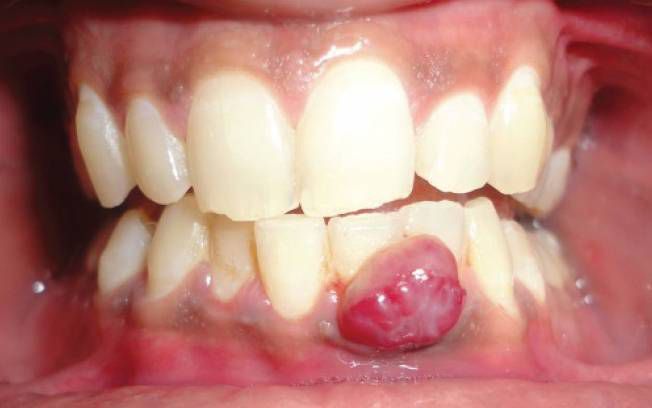

Pyogenic granuloma is a benign growth which mostly occurs at gingiva during pregnancy under the influence of hormones, trauma, or local irritation. These granulomas may develop during the second or third trimester. These lesions are often painless. Reference: https://pubmed.ncbi.nlm.nih.gov/29040143/ Image via: https://www.icliniq.com/articles/dental-oral-health/oral-pyogenic-granuloma